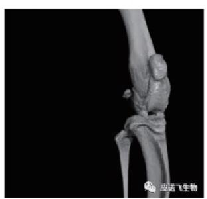

关节组织 生殖器组织